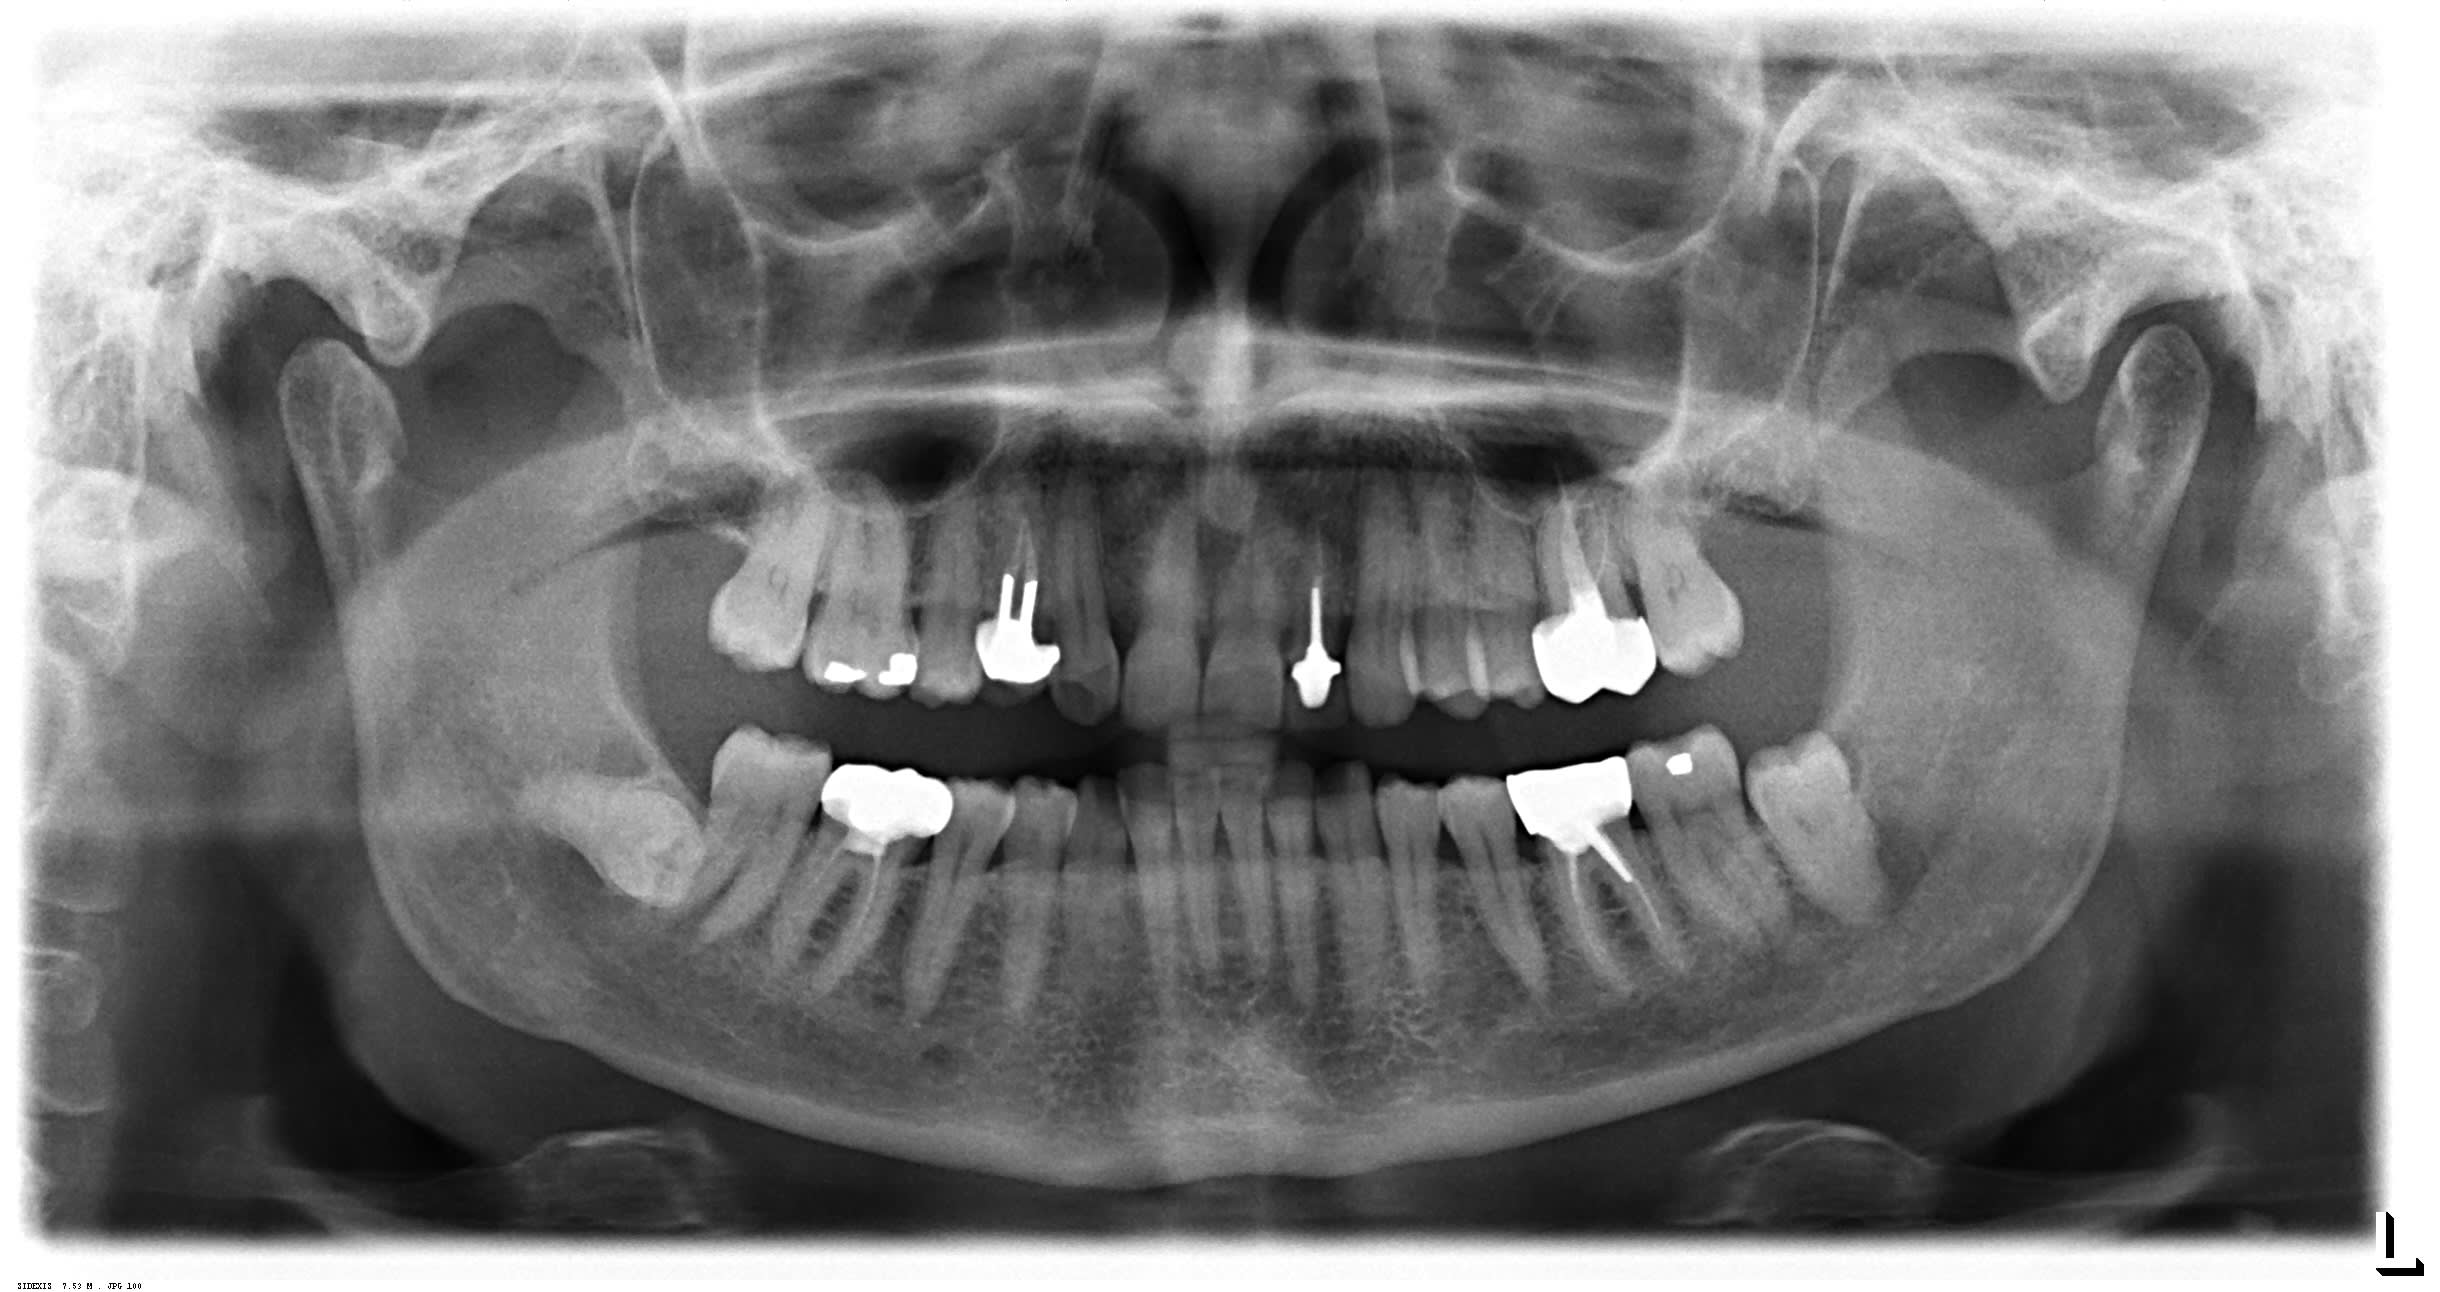

Voila la panoramique!

Sur la pano, on a plus l’impression que c’est la crête distale de la 46 qui est absente.

C’est pas la 48 qui la pousserait ?

oui on dirait . peut etre tout simplement une cc pipée en sous occ .

le plus surprenant , c est que malgré le chaos que l on a prédit du au visuel des usures , , l os ne semble pas avoir morflé . l endo n est pas top et pourtant il n y a pas de granulome non plus ... pour ça que je pensais à la sous occ initiale

Tu noteras la facette d'usure monstrueuse en mésial de 47, j'étais persuadé qu'il y aurait une restauration à la radio, vu la différence en comparaison des sillons conservés en distal.

Le point de départ hypothétique c'est la couronne sur 46 qui aurait entrainé une distoversion de la 47.

Ce qui a projeter dans le plan de l'occlusion la crète mésiale de la 47 créant une interférence.

Pour contourner cette interférence, le patient modifie sa trajectoire vers la gauche, en direction de la fameuse 22.

En parallèle de tout ca, si j'ai bien compris, il y a un délestage de l'occlusion secteur 40, qui induit un réagencement de 44 et 45, poussant 43 vers l'avant.

La 43 boxant la 12 en dehors de l'arcade.

Et si j'ai bien décodé Enlaye souligne également l'usure des entrées de cycle du secteur 30 en réponse à ce qu'on a décrit plus haut.